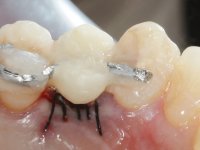

A CT scan was performed to evaluate the available bone heritage and to choose the type and size of implant to be placed. An impression of both jaws was made in alginate, as well as intermaxillary recording for laboratory work on a provisional prosthesis. The provisional prosthesis was made by including a metal wire in a prosthetic tooth adapted to the edentulous space. The root was carefully removed and the implant was placed in the tooth socket corresponding to tooth 1.4. The remaining space between the walls of the alveolus and the implant was filled with regenerative material and then sutured. The prosthesis was previously adapted to the postoperative zone and was then bonded to adjacent teeth. Teflon was used to promote the best possible insulation. Bonding was done using photopolymerizable composite resin using the palatine and inter-proximal walls of the adjacent teeth. After 10 days, the suture was removed and one month later osseointegration was confirmed. Exposure of the implant and placement of the healing screw was performed after 10 weeks. The cervical portion of the provisional tooth had to be reduced to accommodate the healing screw. Stabilized peri-implant soft tissues were impressed using open tray technique with soft and regular consistency putty silicon. In the laboratory the work model was made, along with the choice of pre-fabricated components for the confection of a metal-ceramic crown screwed to the implant with the brand’s interface. Removal of the provisional bridge was done with great care not to touch the interproximal surfaces of the teeth adjacent to the edentulous space. The crown was screwed to the implant, and after imaging, the seating was given the final tightening with 35N of torque. The screw access hole was filled with Teflon and closed with composite resin. The patient manifested satisfaction with the aesthetic and functional rehabilitation achieved.